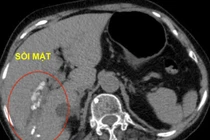

Bệnh lý viêm túi mật cấp do sỏi túi mật thường xảy ra khi sỏi kẹt cổ ống túi mật hoặc sỏi lớn gây tắc nghẽn sự lưu thông của mật, dẫn đến viêm nhiễm,... nếu điều trị không kịp thời có thể dẫn đến suy đa cơ quan.

Nếu không phát hiện và điều trị sớm, bệnh sỏi mật sẽ gây ra nhiều biến chứng nguy hiểm bao gồm: viêm túi mật cấp, nhiễm trùng đường mật, viêm tụy cấp, ung thư túi mật và tắc ruột do sỏi mật.

Đa phần viêm túi mật cấp là do có sỏi. Đây là một trong những bệnh lý cấp cứu ngoại khoa thường gặp ở Việt Nam. Bệnh có thể gây ra những biến chứng nguy hiểm đến tính mạng như nhiễm trùng máu và shock nhiễm trùng đường mật.

Phần lớn sỏi mật lành tính, nhưng khi không phát hiện sớm và can thiệp kịp thời có thể gây tắc mật, dẫn tới nhiều biến chứng nghiêm trọng hoặc ung thư túi mật về sau.

Sỏi túi mật phát hiện rất đơn giản nên mọi người cần chú ý để điều trị kịp thời, ngăn ngừa các biến chứng nguy hiểm. Hiện theo thống kê thì chỉ có khoảng từ 10-20% bệnh nhân có bệnh sỏi mật từ lúc phát hiện ra bệnh tới lúc có triệu chứng là sau 5-20 năm. Còn khi triệu chứng của bệnh, tức là có biến chứng rồi mới đi viện là tình trạng khá phổ biến của những người dân bị mắc bệnh sỏi mật.